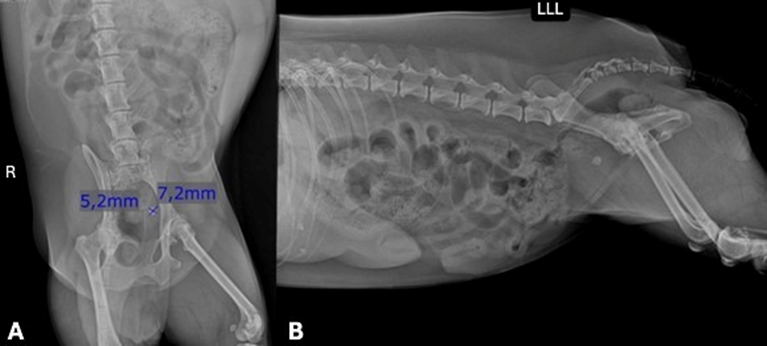

An 8-year-old spayed female Yorkshire Terrier was referred to a specialized nephrology and urology service with clinical signs of hematuria, polyuria, and pollakiuria persisting for one week. The patient, however, had a 7-year history of recurrent cystitis and had previously undergone multiple antibiotic treatments. The dog also had a history of urolith formation. Based on history and clinical signs, hematology, serum biochemistry (urea, creatinine, ALT, AST, ALP, phosphorus, and total proteins), urinalysis, and urine culture with antimicrobial susceptibility testing were requested. Hematology and biochemical parameters were within reference ranges for the species. Urinalysis revealed a urinary pH of 8.0, specific gravity of 1.028, 10–15 red blood cells per high-power field, desquamated epithelial cells, and triple phosphate crystals. Urine culture identified Proteus mirabilis. Abdominal ultrasonography showed bladder wall thickening and irregularity (0.76 cm), with moderate amounts of suspended sediment/debris, echogenic material adhered to the dorsal wall, and a cystic formation with anechoic content and an echogenic wall within the bladder lumen (ureterocele) associated with a calculus measuring 0.78 cm (Figure 1). Dilation of the left ureter (0.36 cm) at its insertion in the trigone region was noted, communicating with the cystic dilation (Figure 1). Abdominal radiographs confirmed the presence of a urolith at the left ureterovesical junction (Figure 2).

Figure 2: A) Ventrodorsal radiographic projection showing a urolith in the urinary bladder. B) Lateral radiographic projection showing a urolith in the urinary bladder.